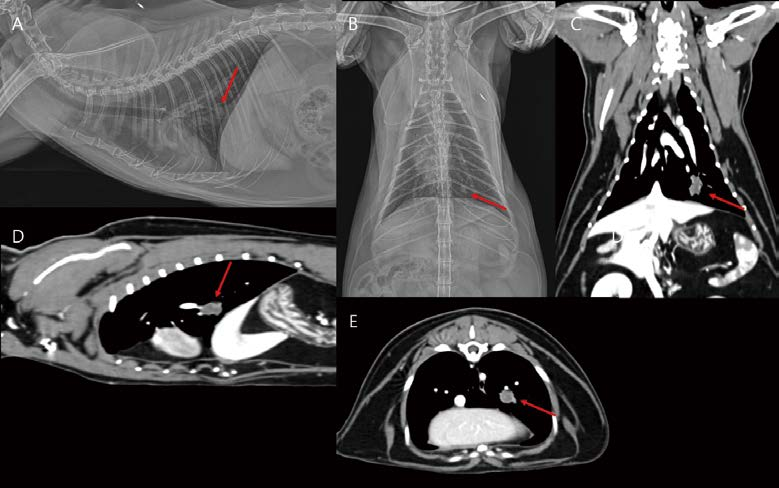

14살 중성화 암컷 4.93kg DSH cat이 식욕부진, 기침 증상으로 내원하였습니다. 흉부방사선 검사 외측상에서 심장의 cranioventral part, 복배상에서 우측 전엽에서 focal하게 기관지, 간질, 폐포의 혼합 침윤 소견이 관찰됩니다(A, B). 흉부 초음파에서 focal consolidation 영역이 관찰되는데, 확장된 기관지로 생각되는 tubular 구조물 내부로 hypoechoic fluid or materials이 채워져 관찰됩니다. 유의적인 혈관 이상 소견은 관찰되지 않습니다(F). CT 검사에서 우측 전엽의 일부에서 bronchial wall thickening, focal한 bronchiectasis, tubular dilated bronchi 내부로 homogeneous hypoattenuating mucoid impaction(mucus plugging) 소견이 관찰됩니다. 사람 asthma 환자에서 잘 관찰되는 finger in glove sign과 유사하게 관찰됩니다(C, D, E, G, H, I). 이 저감쇠 영역은 조영 증강 없이 30~60 HU number로 관찰됩니다. 지방 밀도는 아니어서 exogenous/ endogenous lipoid pneumonia 가능성은 낮게 생각됩니다. Pulmonary hyperinflation, air- trapping, bronchial luminal narrowing 등은 관찰되지 않습니다.

[대한수의사회지 24.png

Feline chronic asthmatic bronchitis 가능성, 종양 가능성, 또는 다른 감염성 질환 배제를 위해 bronchoalveolar lavage를 실시하였습니다. 세포학적 검사에서 호중구, 호산구 모두 주로 관찰되며, 종양성 변화는 관찰되지 않았습니다. PCR, 배양 검사 모두 음성으로 확인되었습니다. 흔히 하부 호흡기 질환을 크게 2개의 카테고리로 분류하는데, 고양이 asthma는 spontaneous reversible bronchoconstriction, airway remodeling, eosinophilic airway inflammation을 보이고, 고양이 chronic bronchitis는 airway thickening, excessive mucus production, neutrophilic inflammation을 보입니다. 그러나 이 환자처럼 세포학적으로도 eosinophilic, neutrophilic inflammation 둘 다 관찰되고, 영상학적으로도 소견이 overlapping되는 chronic asthmatic bronchitis 증례가 많습니다. 따라서 feline chronic asthmatic bronchitis에 준해서 스테로이드 포함 대증 치료를 진행하였습니다. 환자는 내과적 치료에 잘 반응하여 기침, 식욕, 활력 모두 개선되었으며, 흉부 방사선 검사에서 병변의 범위와 밀도가 약간 감소(병변이 아직 남아 있음) 하였습니다. 그러나 6개월 후, 기침이 다시 증가하고, 호흡하는데 불편함을 호소하였습니다. 흉부 방사선에서 우측 전엽 침윤의 범위와 밀도 모두 유의적으로 증가하여 종괴 양상으로 관찰됩니다(A, E. 사진 C는 6개월 전 초진 시, 사진 D는 스테로이드 처치 후, 사진 A, E는 초진 6개월 후). 병변은 폐초음파 검사에서 예전보다 크기가 크고 균질한 저감쇠 종괴 양상으로, bronchial wall, 혈관 구조 모두 소실되어 관찰됩니다(G). CT를 재촬영했을 때 석회화된 기관지벽의 right lateral, ventral로 다소 저감쇠의 종괴가 bulging되어 관찰됩니다(B, F, H, I). 초음파 가이드 FNA에서 pulmonary lymphoma가 고려되었고, 종괴를 포함한 우측 전엽절제술을 실시하였습니다. 조직병리학 검사에서 폐종괴는 괴사, histiocytic inflammation, multifocal bronchiectasis with mucus impaction and osseous metaplasia를 동반한 poorly differentiated round to polyhedral cell neoplasm로 나왔습니다. 추가 면역 염색(CD3, Pax-5, Iba-1, E-cadherin)이 추천되어 진행하였고 diffuse large B cell lymphoma로 확진하였습니다.